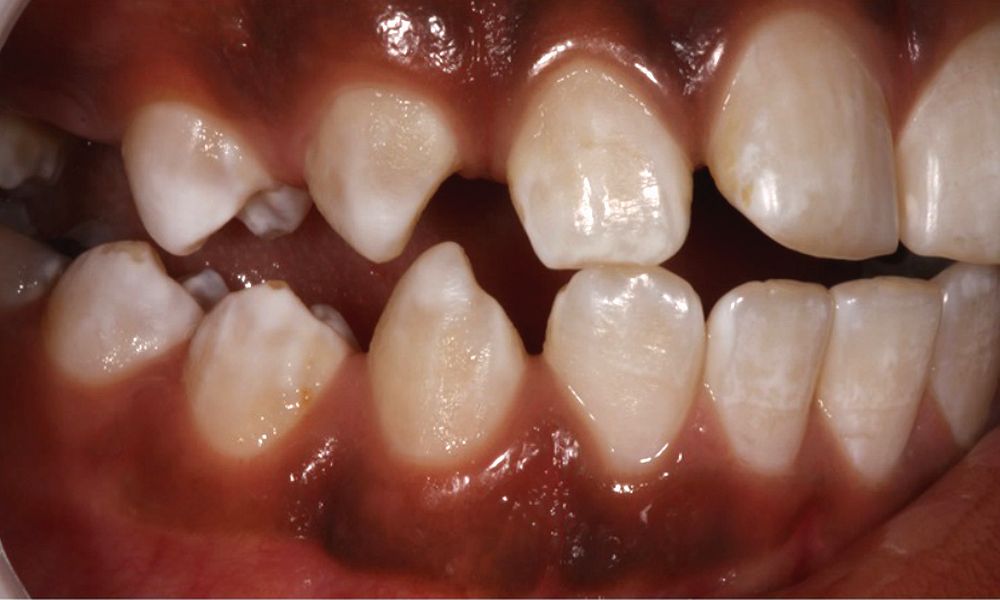

Dental Fluorosis Degree . at higher levels of fluoride exposure, the white lines in the enamel become more and more defined and. dental fluorosis is caused by the excessive ingestion of fluoride during tooth. dental fluorosis (df) is classically characterized by the stains. based on this paradigm, public health dentists argued that fluoride should be ingested during tooth formation. dental fluorosis occurs as a result of excess fluoride ingestion during tooth formation. dental fluorosis is a developmental disturbance of dental enamel, caused by successive exposures to high.

Degree of dental fluorosis in children between the ages of 8 and 15

Degree of dental fluorosis in children between the ages of 8 and 15 Dental Fluorosis Degree dental fluorosis occurs as a result of excess fluoride ingestion during tooth formation. dental fluorosis is a developmental disturbance of dental enamel, caused by successive exposures to high. at higher levels of fluoride exposure, the white lines in the enamel become more and more defined and. dental fluorosis is caused by the excessive ingestion of fluoride. Dental Fluorosis Degree.